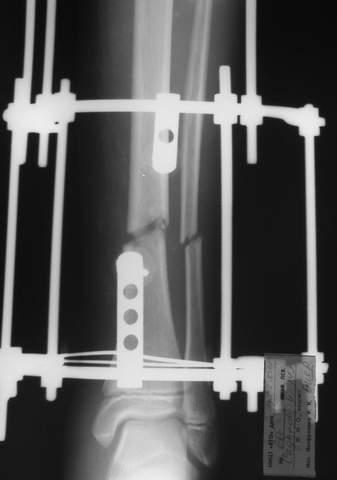

В аттачте № 3 - один из примеров полукольцевого аппарат...

Это уже я баловался.

Итог? Работы больше (по времени и

интраоп "подгонке"), срастается также, а особого преимущества по сравнению с

"чиста" кольцевым (вес, удобство ношения и пр.) - я, по крайней мере,

не нашел.

Теперь не балуюсь.

Может быть зря?

3a

3b

3c